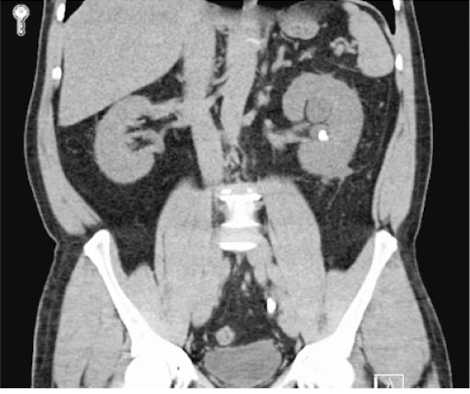

What is this

Renal Calculi